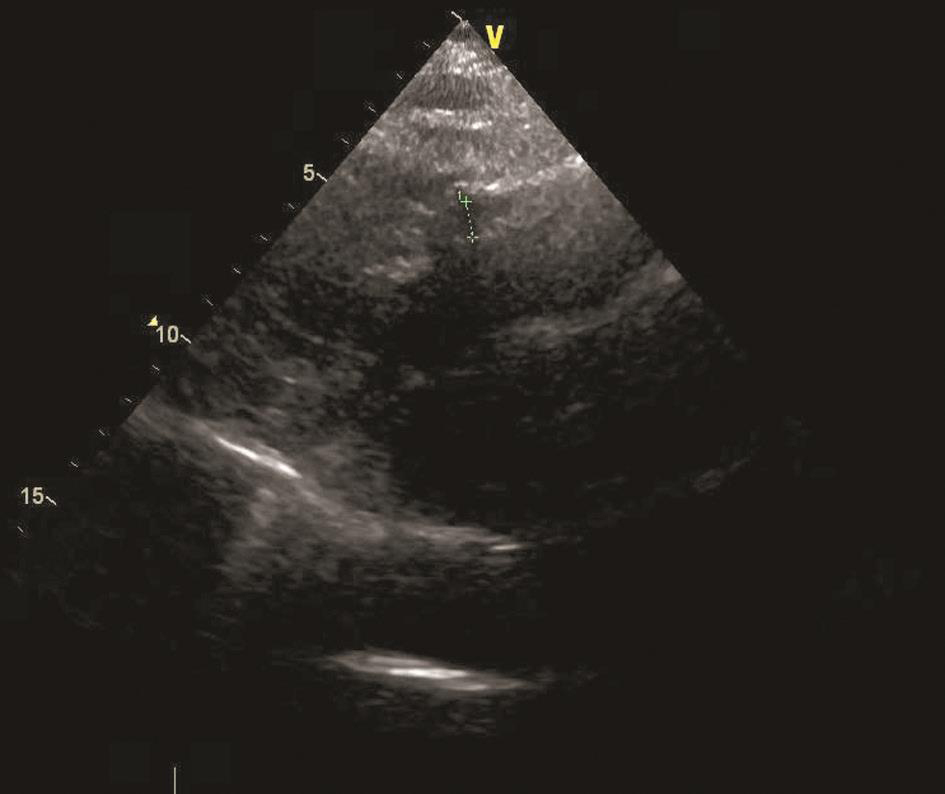

既往检查结果如下:2012年10月,心脏彩超示人工主动脉瓣及管道与主动脉根部前缘可见约直径0.68cm的漏口(图4);左心造影示环主动脉根部假性动脉瘤,漏口位于左前方可能性大;胸主动脉CTA示主动脉瓣区升主动脉根部术区造影剂外渗(图5)。2013年11月,复查胸主动脉CTA提示升主动脉漏口较前明显增大(直径约1.2cm)。2015年5月,心脏彩超示人工主动脉与主动脉前壁间血流信号,考虑术后再次出现瓣周漏(图6);胸主动脉CTA示主动脉根部造影剂漏出,形成一假性动脉瘤,升主动脉上部部分管壁增厚伴溃疡(图7);实验室检查示血沉35mm/h、C反应蛋白35.2mg/dl,抗链球菌溶血素86U/ml,降钙素原正常。

图6 心脏彩超(2015-05)